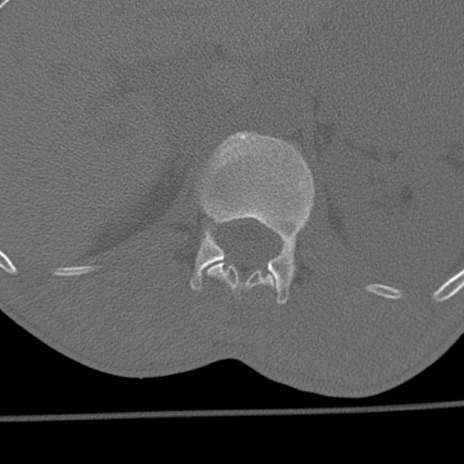

症例3 腰椎CT(横断像)

腰椎CT